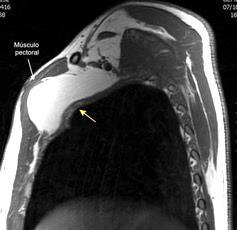

48 MASAS. LIPOMA SUBPECTORAL

Densidad similar al músculo con estriaciones internas de grasa

Hallazgo incidental . Región infraescapular 2% de TC del tórax. Bilateral 60%.

Burt AM et al. Imaging review of lipomatous musculoskeletal lesions. SICOT J2017/ Murphey MD et al. From the archives of the AFIP: benign musculoskeletal lipomatous lesions. Radiographics. 2004

Isointenso con grasa subcutánea